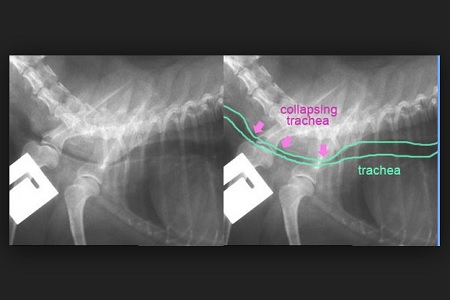

Il collasso tracheale può essere definito come una insufficienza respiratoria conseguente allo schiacciamento di una o più porzioni della trachea, il cui lume risulta così ridotto, impedendo all’aria di giungere correttamente fino ai polmoni.

In alcuni animali, gli anelli che compongono la trachea si indeboliscono sempre di più con il passare del tempo fino a schiacciarsi, restringendo così il lume della trachea. In poche parole, sembra quasi che la cartilagine non riesca più a mantenere la forma più o meno cilindrica, creando piuttosto un tubo che si ripiega dall’alto verso il basso. In questo modo l’aria non riesce più ad arrivare facilmente ai polmoni, provocando una difficoltà respiratoria più o meno grave.

Un collasso tracheale è abbastanza semplice da riconoscere, proprio perché il “verso d’anatra” è tipico di questo problema. Oltre alla visita clinica, il veterinario effettuerà una radiografia per verificare la presenza di un restringimento della trachea.